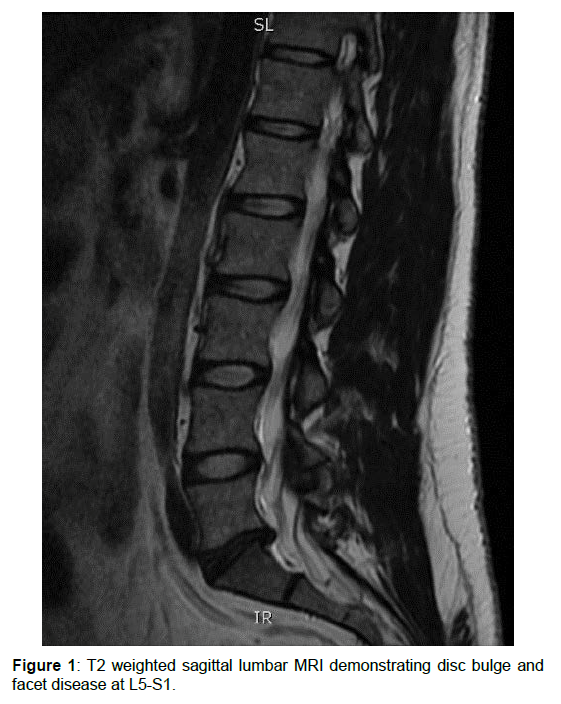

36歲女性,國民警衛隊。六年的下背疼痛,肇因於一次舉重受傷。久坐和比較激烈的活動會讓她的腰痛惡化;經歷各式保守治療和注射治療均無效。理學檢查顯示,腰椎前彎會使她更加疼痛;同時腰椎兩側肌肉有多處壓痛。下肢無神經方面的病變。核磁共振顯示L5S1椎間盤變黑且突出,同時椎間盤厚度已變薄。